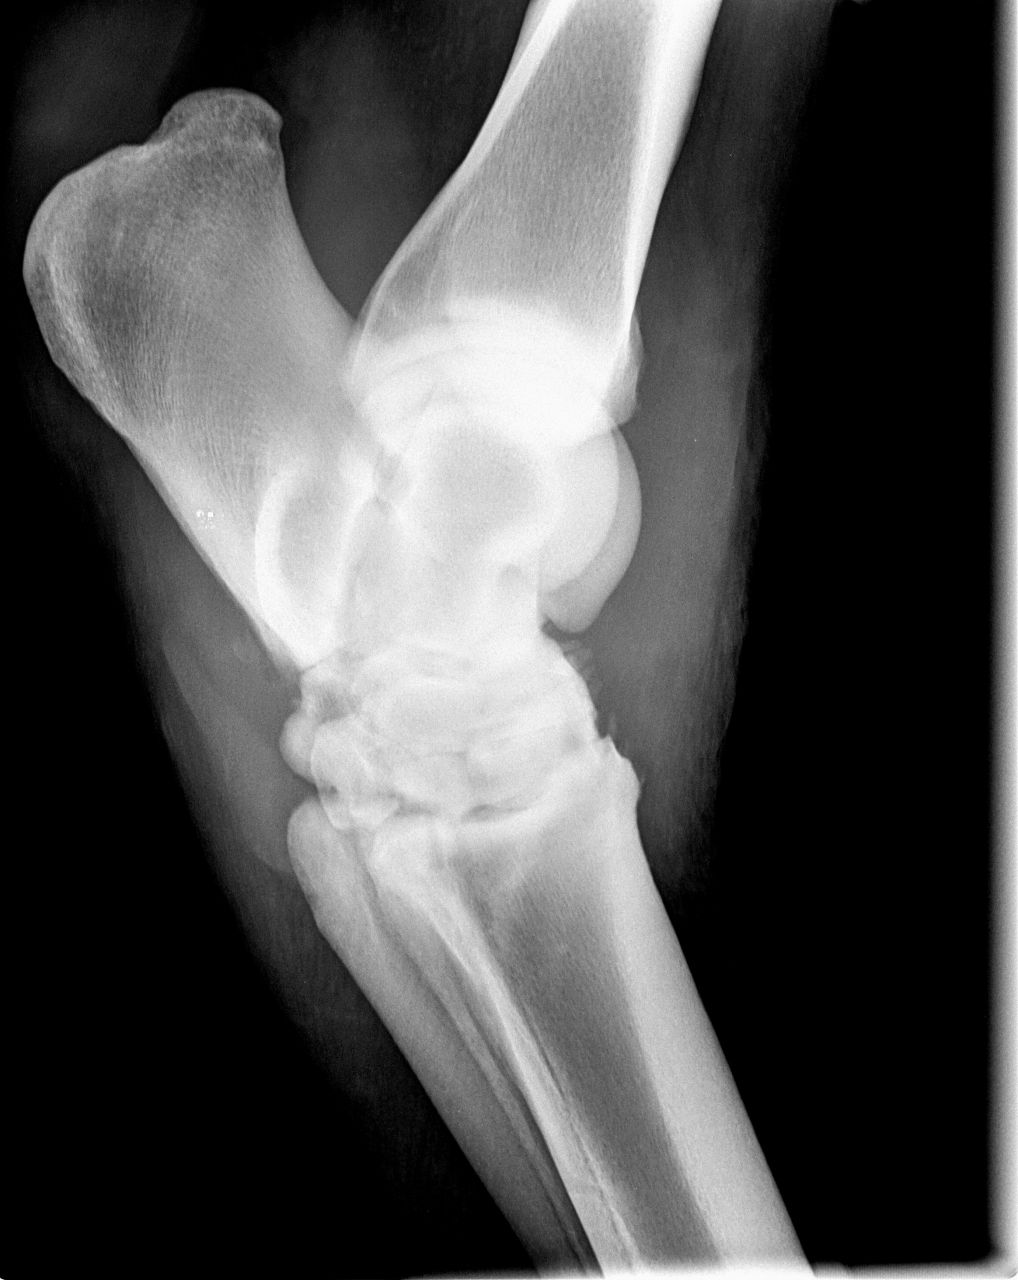

| Dire merci | Voici une radio prise en octobre 2010, [url=https://www.1cheval.com/membre/services/photos/images/191702.jpg" class='zoombox zgallery3279789' ] ![]() et une en décembre : [url=https://www.1cheval.com/membre/services/photos/images/191703.jpg" class='zoombox zgallery3279789' ] ![]() comme tu vois, c'était pas joli joli ! |

| Dire merci | je ne sais pas comment on fait pour entourer. Mais si on regarde tout les pourtours de ses articulations du jarret ne sont pas nets, il y a de l'arthrose et des détachements osseux. En faite, ca s'est décalcifié de partout et ca s'est recalcifié comme ca a pu et ca a fait une arthrodèse du jarrêt (sur le second cliché, on ne distingue plus vraiment les os, ca fait des blocs) |

| Dire merci | Voici 2 autres clichés encore plus parlant : en octobre : [url=https://www.1cheval.com/membre/services/photos/images/191705.jpg" class='zoombox zgallery3279806' ] ![]() en décembre : [url=https://www.1cheval.com/membre/services/photos/images/191706.jpg" class='zoombox zgallery3279806' ] ![]() oh, tu sais, aujourd'hui, j'en parle s'en soucis et en étant contente du résultat, mais au moment où, je suis passé par des questionnements et des remises en cause pas possible, est ce que je fais bien, est ce que j'ai raison, ne devrais-je pas écouter les autres et ne pas m'acharner, etc...? sauf que les autres, ils ne sont pas à ta place, alors, j'ai écouté mon instinct. financièrement, j'y ai laissé des plumes, heureusement, les dépenses étaient étalées car dur avec un smic. Et pis, ben une fois qu'on a commencé, on va jusqu'au bout, pas possible à mi-parcourt d'arrêter, vaut mieux alors ne pas commencer. Je comprends par quoi tu passes. La fêlure de ton cheval n'est pas si grave que ca. Evidemment, c'est un mot impressionnant, surtout qu'on associe facilement chez le cheval fracture= fichu. Qu'est il envisagé comme soins pour ton cheval? Qui est-il? A quoi est-il destiné? |

| Dire merci | Chez ma jument, ce n'est pas une fracture au sens on on l'entend, c'est à dire une cassure de l'os. C'est plus une facture au sens large du terme, où on prend en compte la globalité de l'articulation. On voit qu'il y a pleins de petits éclats, qu'il n'y a plus d'espace entre les os et qu'ils se soudent entre eux. Désolée, je ne suis pas véto, j'explique avec mes mots, je ne suis pas précise. |